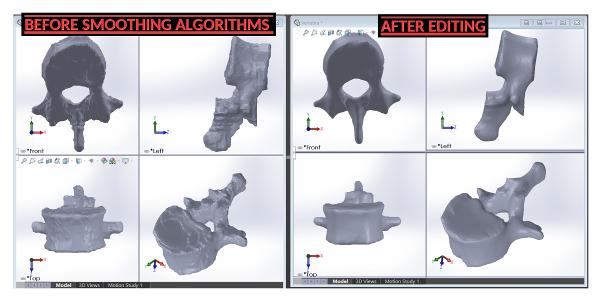

TRINOTA aims to help doctors assess patient specific treatment efficacy with the use of 3D visualization (Physical and Digital Models) of a patient's region of interest (ROI).

With the use of our Ultra High Resolution Professional Grade 3D Printer, we can produce physical models of the patient's ROI.